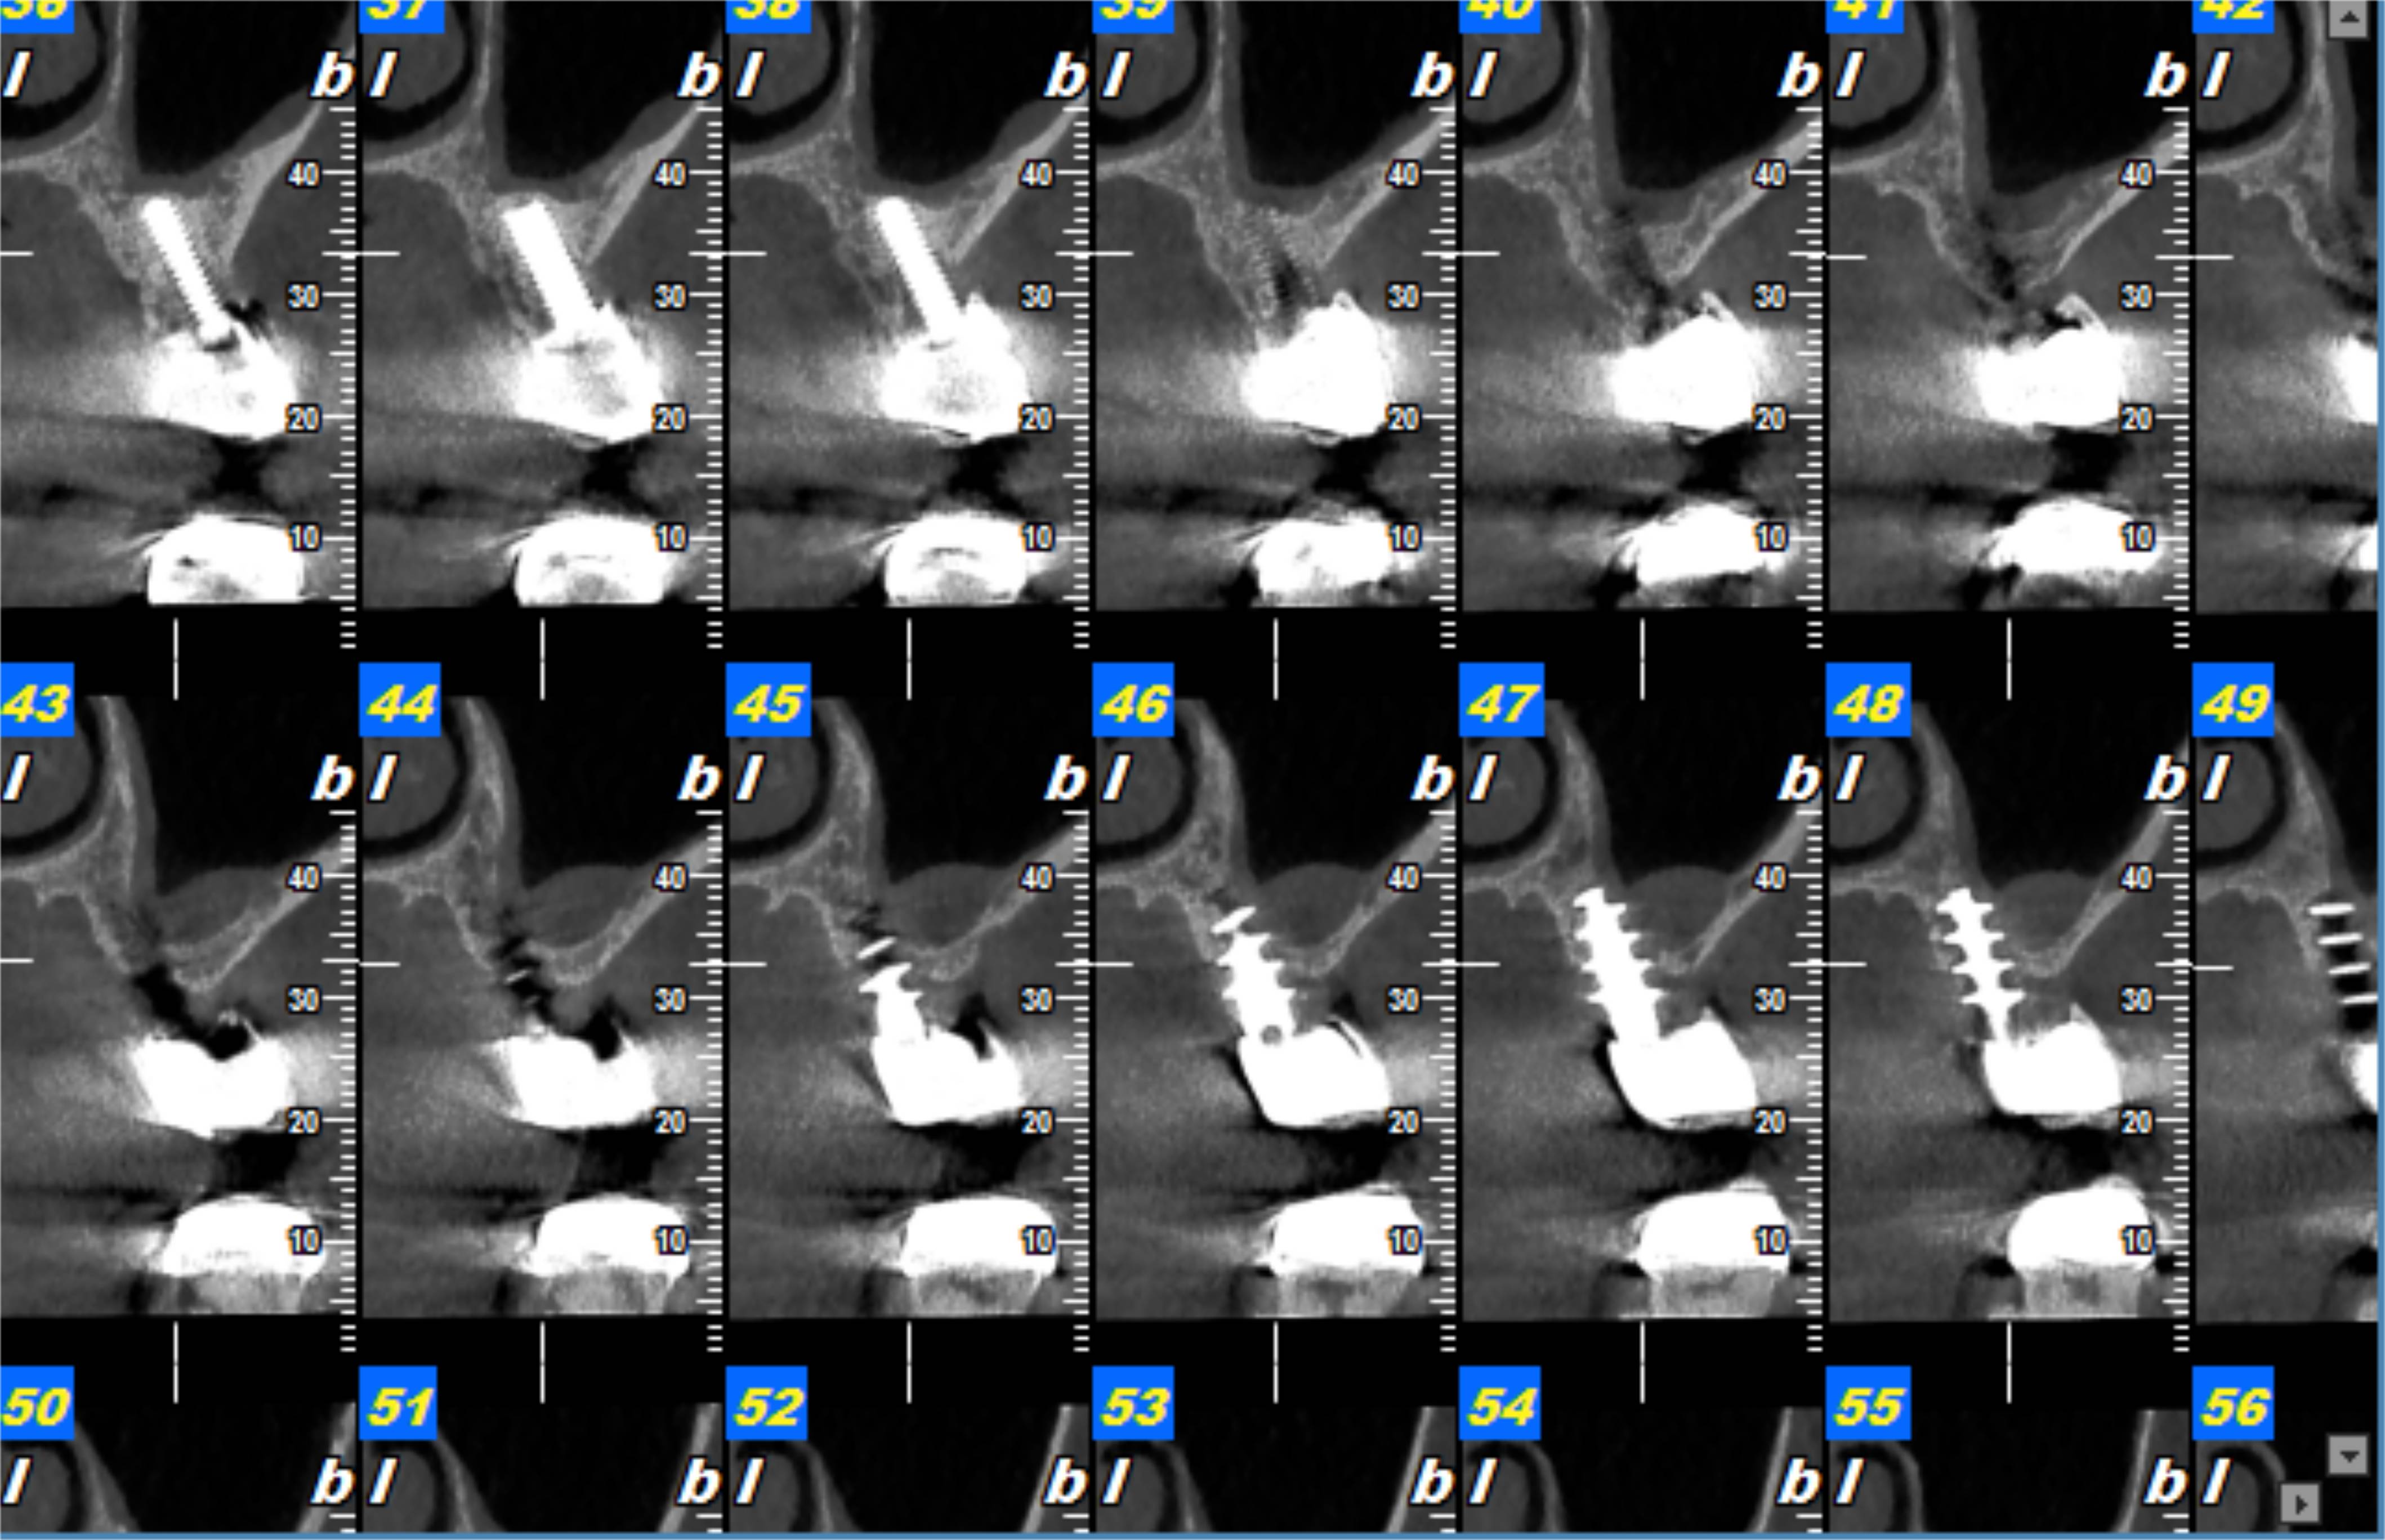

Desde Institutos Guirado apostamos por una comunicación transversal con el profesional dental, adaptándonos a sus preferencias y poniendo a su disposición el Software NNT, para que pueda planificar el acto intervencionista con las imágenes del paciente y reproducir el resultado en 3D, herramienta que le facilita la exposición de la intervención y los resultados para dar un mejor servicio a su paciente.

Hasta ahora, determinar el grado de osteointegración de un implante podía llegar a resultar complicado, ya que el artefacto metálico producido por elpropio implante no permitía ver con nitidez la zona.

Gracias a la tecnología CBCT con sus características de exposición y algoritmos de la reconstrucción de la imagen consiguen una disminución significativa del artefacto metálico en comparación con los TC convencionales.

De esta manera, el estudio por CBCT se vuelve imprescindible tanto para el estudio de planificación para implantología como para control de osteointegración una vez implantado.